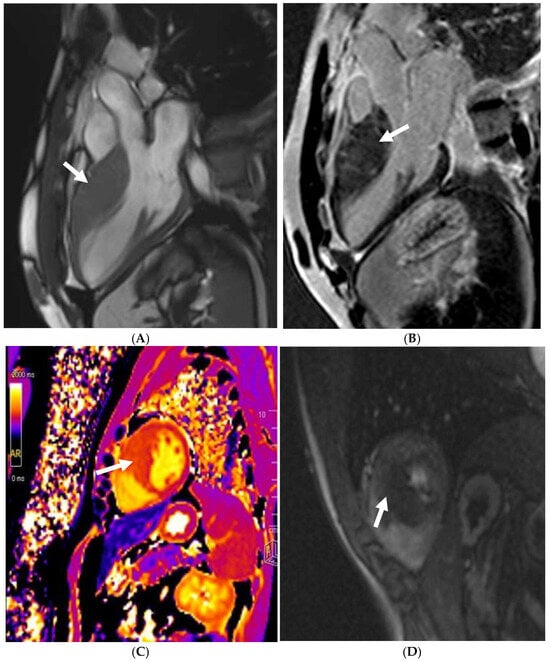

Non-ischaemic replacement fibrosis or fatty replacement in the presence or absence of LV dysfunction (LV EF < 50%) or regional wall motion abnormalities constitute the main imaging findings required for an NDLVC diagnosis. Cine imaging, T1 mapping, and LGE imaging should be performed if there is suspicion of NDLVC. The presence of LGE in NDLVC is why cardiac MRI is key when evaluating athletes with NDLVC. Similar to DCM, an inflammatory (acute or chronic myocarditis) or genetic component (DSP, FLNC, Desmin [DES], Phospholamban [PLN], LMNA) are the main drivers towards myocardial fibrosis in NDLVC [75]. The extent and degree of scarring again offers substantial prognostic information, similar to the DCM phenotype (Figure 6).

Figure 6. A 21 year old endurance athlete, referred for screening as her mother was diagnosed with arrhythmogenic cardiomyopathy secondary to a Desmoplakin pathogenic variant. The athlete was also gene-positive, with a normal ECG and echocardiogram. Cardiac MRI identified a ring-like subepicardial scar on post-contrast imaging (A), with a diffusely elevated T1 (B), resulting in a diagnosis of non-dilated left ventricular cardiomyopathy.

The NDLVC may also act as a precursor to DCM. The presence of non-ischaemic fibrosis predating LV dilatation and/or dysfunction is well established [85]. Unexplained ventricular arrhythmias may also be the manifestation of early concealed cardiomyopathy [86], hence why cardiac MRI to rule out scarring is pivotal in these patients.

Cine SSFP imaging plays a key role in determining RV volume and function. An axial stack of the whole heart, with a reasonably small interslice gap, may also help identify subtle regional wall motion abnormalities in the RV free wall. LGE imaging has been incorporated in the proposed Padua Criteria when there is a suspicion of biventricular arrhythmogenic cardiomyopathy (see previous section) [97]. LGE to rule out RV scarring is, however, often limited in efficacy, as the fibrosis is often very subtle due to the thin-walled RV wall. As discussed previously, RV insertion point fibrosis is frequently observed in athletes and is not a marker of disease (Figure 7).

Figure 7. An 18 year old male Caucasian competitive swimmer who was seen because of a very long PR interval in the context of non-cardiogenic syncope. Echocardiography revealed a dilated LV. This was confirmed on CMR, though perfectly within normal athletic specific reference ranges. Post-contrast imaging showed posterior RV insertion-point fibrosis.